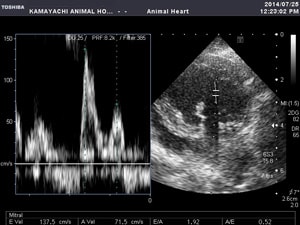

超音波(エコー)検査

心臓内部の大きさや構造の異常の把握、心機能の評価に有効な検査です。この検査により、心臓病の種類、重症度などを把握することができます。

犬の心臓病の75%が僧帽弁閉鎖不全症です。マルチーズやトイプードルなどの小型犬やキャバリアに多くみられる病気です。加齢に伴って心臓の左心房と左心室の間にある僧帽弁がきちんと閉まらなくなり、血液が逆流し左心系に血液が鬱滞することによって症状が現れます。病態が進行すると、肺水腫を起こし呼吸困難になり、喉にものがつかえたような咳をしたり、運動したがらなくなったりします。治療は薬剤投与による内科的治療が主であり、今現れている症状をできるだけ抑えてQOL(生活の質)の改善を目指します。また、近年は外科的治療も行われるようになっています。

左心房の拡大と僧帽弁の逸脱

僧帽弁領域で血液の逆流がみられる

心機能の検査

血液の流速の測定